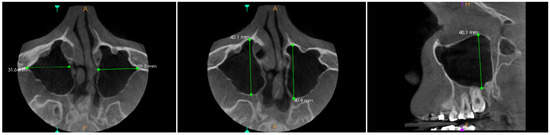

Background/Objectives: The aim of this study was to develop a novel Nasal Spine-Guided Classification for assessing the alveolar vertical extension of the maxillary sinus and to evaluate its anatomical relationship with the roots of the posterior teeth using CBCT in a Saudi [...] Read more.

Background/Objectives: The aim of this study was to develop a novel Nasal Spine-Guided Classification for assessing the alveolar vertical extension of the maxillary sinus and to evaluate its anatomical relationship with the roots of the posterior teeth using CBCT in a Saudi subpopulation. Methods: Maxillary sinus pneumatization was measured using cone-beam computed tomography for 380 patients. The assessment was performed along a horizontal plane extending between anterior and posterior nasal spine. In addition, pneumatization was evaluated in edentulous areas, and between the roots of multi-rooted teeth. Maxillary sinus membrane thickness was also measured. The results were expressed as mean, median and interquartile range, and considered statistically significant at a p-value < 0.05. Results: The mean maxillary sinus pneumatization on the left side was 8.8 ± 4.32 mm, and 8.58 ± 4.85 mm on the right side, with no statistically significant difference. The median of pneumatization in the edentulous area and between the roots on left side were 5.1 and 3.8 mm respectively, while on the right side, the median pneumatization was 5.03 and 3.04 mm. In addition, the proximity of the maxillary root apices to the sinus floor revealed a zero distance in 80.49% of the roots on the left side and in 79.48% on the right side. Furthermore, the results indicated no statistically significant association between maxillary sinus membrane thickness and pneumatization in the edentulous area. Conclusions: CBCT analysis revealed a predominance of advanced maxillary sinus pneumatization (Class III) and a high frequency of direct contact between posterior maxillary root apices and the sinus floor in the studied population. Additionally, no significant association was identified between maxillary sinus membrane thickness and sinus pneumatization in edentulous areas. Full article

Show Figures

Figure 1